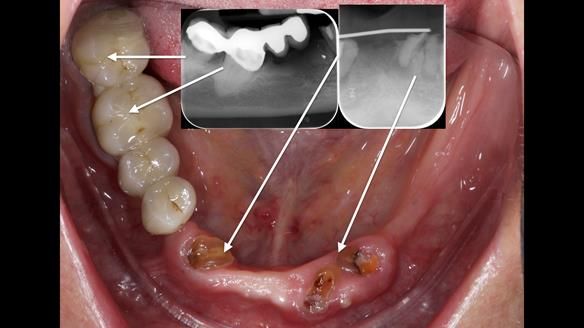

However, once Rowan and I reviewed the remaining metal crown on tooth 46, we realised it would make an ideal abutment for a gasket denture. By reshaping the lingual surface of the crown, we created an excellent gasket seal.

This approach worked far better than the proposed ring-clasp design - improving retention, comfort, and aesthetics while keeping the design clean and simple.

- The gasket seal around 46 was made using retention.sil 200, producing a precise, cushioned fit.